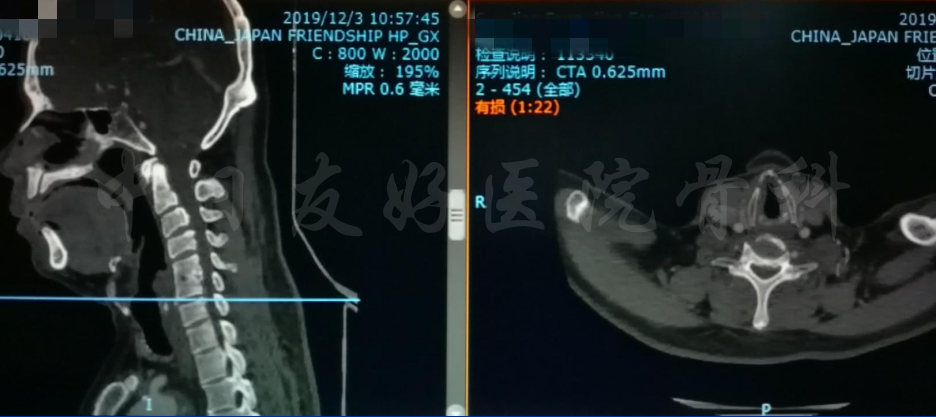

影像学检查

颈椎X片

颈椎MRI

颈椎MRI

颈椎各节段MRI(上下滑动)

颈CT(上下滑动)

腰椎MRI